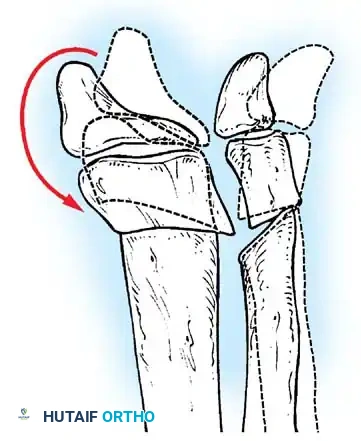

Knee Deformities

Knee deformities typically present as either flexion or extension contractures.

* Extension Contractures: Common in high-level lesions. Treated with V-Y quadricepsplasty if interfering with seating.

* Flexion Contractures: Common in L3-L4 lesions due to unopposed hamstrings. Contractures >20 degrees interfere with bracing and ambulation.

Knee Flexion Contracture Release

Surgical Management:

Mild contractures are managed with hamstring lengthening and posterior capsulotomy. Severe, rigid contractures in older children may require a distal femoral anterior closing-wedge extension osteotomy.

Distal Femoral Extension Osteotomy